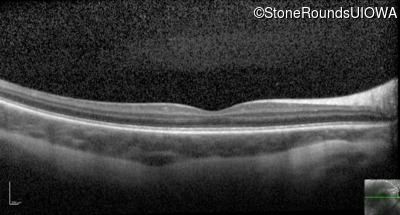

Optical Coherence Tomography - Left - 10/200

Exemplar / OCT Stack